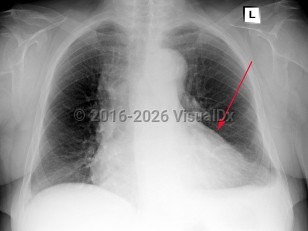

Pericarditis

Symptoms and Signs: Acute pericarditis typically presents with sharp pleuritic chest pain, exacerbated by the supine position and improved with leaning forward. Fever and myalgias may be present but are not required features. On examination, a scratch-like friction rub (pericardial rub) may be heard, although this is present in less than 33% of cases. To make the diagnosis of pericarditis, the patient must have 2 of 4 criteria: pericardial rub, chest pain, ECG changes, and/or presence of a pericardial effusion. Chest pain has the highest incidence and is seen in 85%-90% of cases.